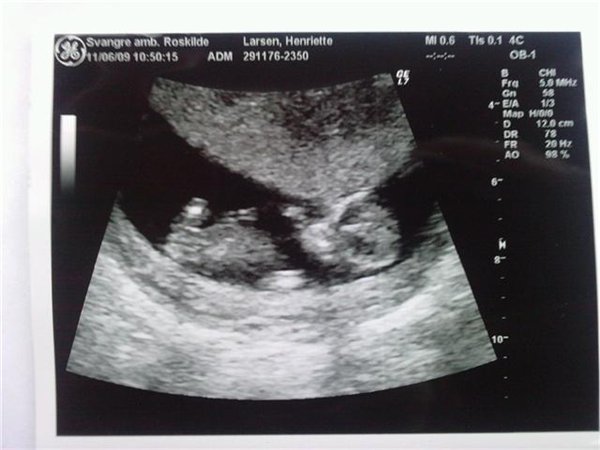

talle var 435 udfra en aldre på 32 år små ryger,højte 163 vægt før gravid 50,5 nu 60,4 kunne hun oplyse.

Men med min scanningen også var= 2340.

Nakkefolden var 1,2 mm.

Ret flot lille sagde hun.